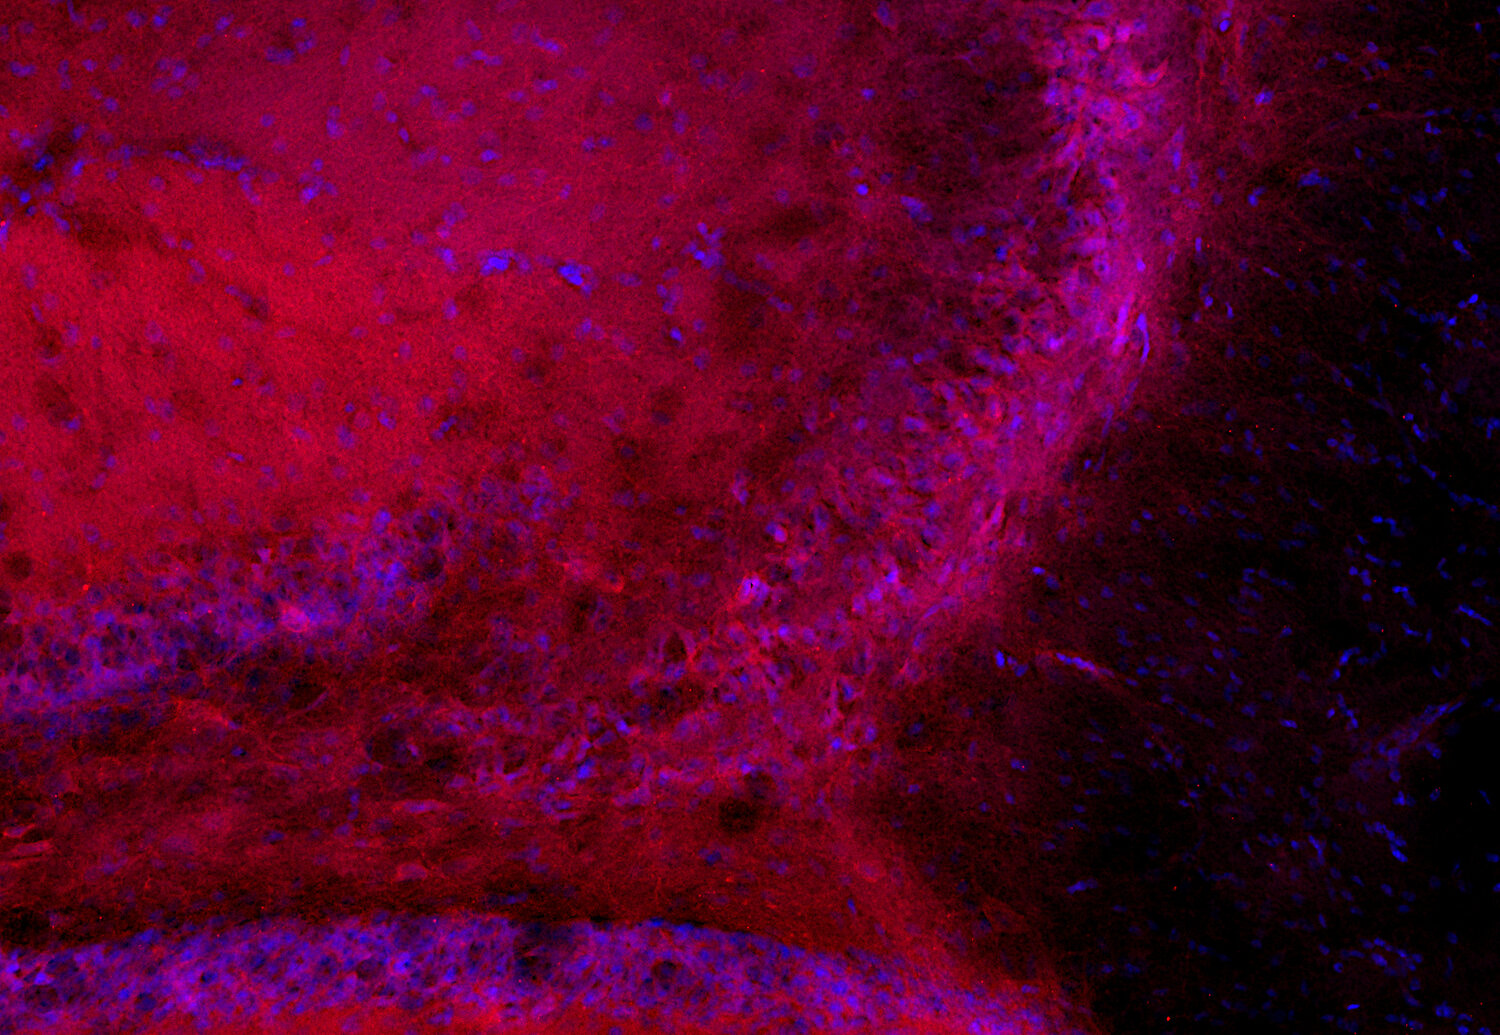

GABA-A receptor beta2 antibody - 224 805

IHC: 1 : 500 gallery

IHC-Fr: 1 : 500 (see remarks) gallery

IHC-G: 1 : 500 (see remarks) gallery

Immunohistochemistry (IHC) on 4% PFA perfusion fixed tissue with 24h PFA post fixation. Immunoreactivity is usually revealed by fluorescence or a chromogenic substrate. Some antibodies require special fixation methods or antigen retrieval steps. For details, please refer to the ”Remarks” section.

Immunohistochemistry on fresh frozen (IHC-Fr) cryo-tissue-sections. In contrast to standard PFA perfusion fixed tissues, fresh frozen cryo-tissue-sections can be variably postfixed with alcohols, acetone or PFA. Alcohol or acetone fixation is e.g. of advantage for antigens masked by PFA crosslinking. For recommended postfixation, please refer to the ”Remarks” section. Immunoreactivity is usually revealed by fluorescence or a chromogenic substrate.

Immunohistochemistry on glyoxal fixed (IHC-G) tissue. The tissue is perfused with saline and afterwards immersion fixed with a glyoxal solution. For details of the glyoxal solution, please refer to the remarks section. Immunoreactivity is usually revealed by fluorescence.

Immunogen Recombinant protein corresponding to AA 343 to 430 from rat GABA-A receptor β2 (UniProt Id: P63138)

Reactivity Reacts with: rat (P63138), mouse (P63137).